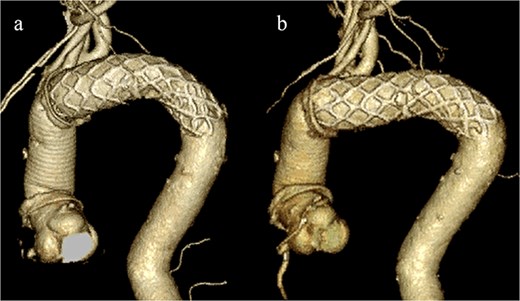

An 83-year-old man presented at our hospital with intermittent hemoptysis. Two years before, he had undergone total arch replacement with FET insertion using a 29 × 120 mm Frozenix J graft (Japan Lifeline, Tokyo, Japan) for a 55 mm aortic arch aneurysm. The Frozenix J graft is a commercially produced open stent graft with an internal skeleton made of nickel-titanium alloy. One year after surgery, postoperative contrast-enhanced computed tomography (CT) showed a reduction in the aneurysm diameter to 49 mm, with no endoleaks (Fig. 1a).

(a) Contrast-enhanced CT 1 year after total arch replacement with FET showing a reduction in aneurysm diameter from 55 mm to 49 mm, with no evidence of endoleak. (b) Contrast-enhanced CT 2 years after total arch replacement with a FET, showing an increase in aneurysm diameter to 56 mm.

CT revealed no endoleak, but the aneurysm had enlarged to a diameter of 56 mm (Fig. 1b). Three-dimensional CT revealed straightening and proximal migration of the FET (Fig. 2). No clear signs of pulmonary parenchymal hemorrhage or findings suggestive of the mass were reported. Laboratory tests indicated mild anemia, with a hemoglobin of 9.7 g/dL and hematocrit of 29.0%. No infectious or inflammatory diseases that could cause hemoptysis were identified.